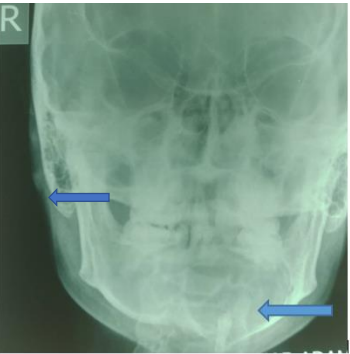

The plain radiographs of the jaw (Anterior-Posterior and left lateral views) demonstrated a lucent well circumscribed swelling with sclerotic margin over the crown and root of an unerupted tooth on the left lower hemi-mandible most likely the third molar; this is most likely the circumferential form of the dentigerous cyst (Figures 1 and 2). No dental anarchy or loss of the lamina dura was noted on the jaw radiograph. The patient had surgical excision of the jaw mass and unerupted/impacted tooth with histopatholgical assessment of the sample that confirmed the epithelial lining likened to dentigerous cyst.

Figure 1: An anterior-posterior view of the jaw demonstrating a well circumscribed oval lucency with sclerotic margin over the crown and root of an unerupted tooth in the region of the body of the left hemi-mandible in keeping with the classical appearance of a circumferential form of dentigerous cyst (Left blue arrow).

Figure 2: A left lateral view of the jaw demonstrating a well circumscribed oval lucency with sclerotic margin over the crown and root of an unerupted tooth in the region of the body of the left hemi-mandible in keeping with the classical appearance of a circumferential form of dentigerous cyst (right blue arrow).